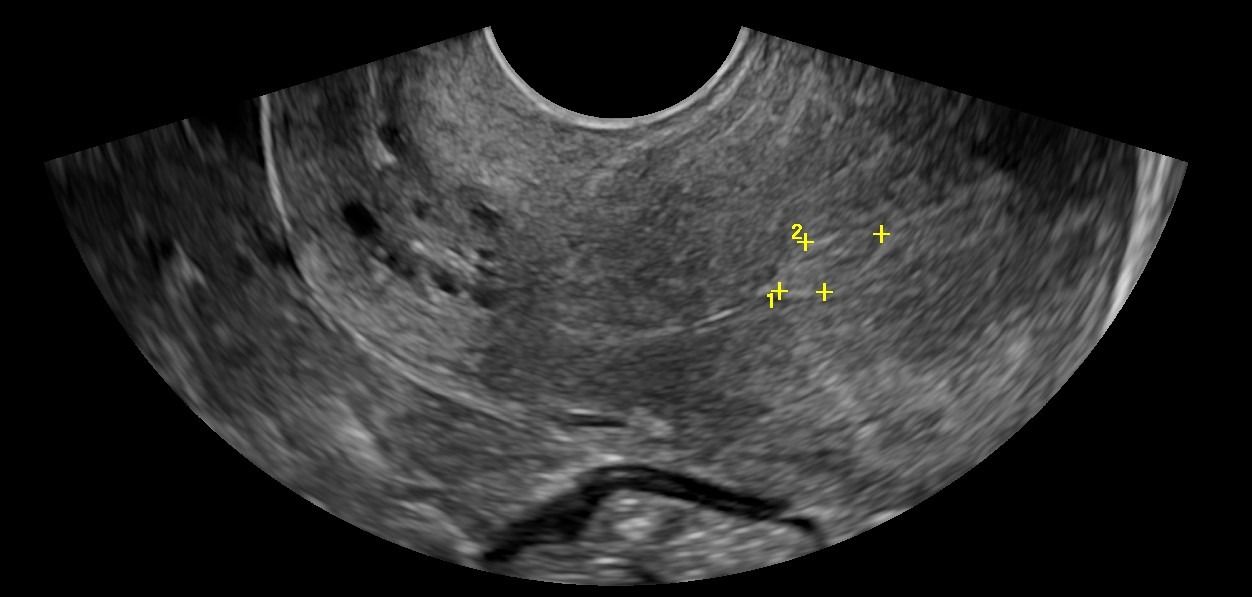

- Μήτρα: Με το Διακολπικό Υπερηχογράφημα, μπορεί να αξιολογηθεί το μυομήτριο και να εντοπιστεί η παρουσία ινομυωμάτων. Το πάχος του ενδομητρίου μπορεί να μετρηθεί με ακρίβεια, κάτι που είναι κρίσιμο τόσο για γυναίκες αναπαραγωγικής ηλικίας όσο και για γυναίκες μετά την εμμηνόπαυση ή μετά από θεραπευτικά σχήματα για νεοπλάσματα.

- Ακρίβεια: Για την ακριβή μέτρηση του πάχους του ενδομητρίου και την αξιολόγηση της ωοθηκικής δομής, το Διακολπικό Υπερηχογράφημα παρέχει σαφέστερα αποτελέσματα σε σχέση με το υπερηχογράφημα κάτω κοιλίας.